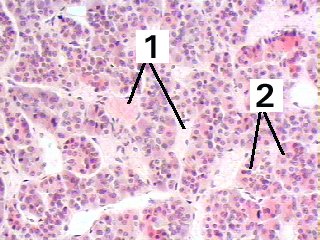

| Pituitary gland | Slide 52 (H & E) |

A high magnification of the pars anterior of the pituitary gland demonstrating the arrangement of the glandular cells in groups around the sinusoids.

Fig 52-007 Wheater 3rd Ed p.306-307 or 4th Ed p.96 |